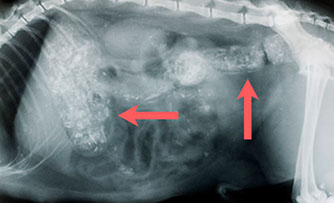

Knochenkot im Magen und Darm eines Hundes nach Grillparty